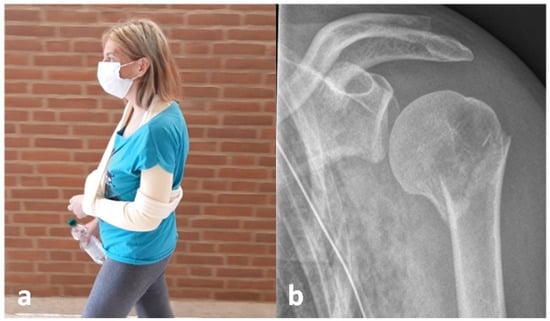

2.3. Exemplary Case Presentation